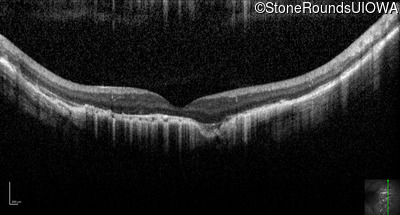

Optical Coherence Tomography - Right - 20/200 -1

Exemplar / OCT Stack

OCT Stack